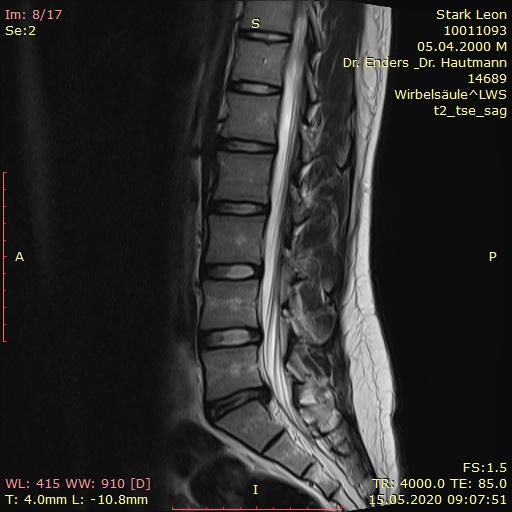

MRT Bilder LWS erste Einschätzung?

Wer kann mir etwas zu meiner LWS sagen? (Bandscheibenvorfall, MRT Befund)

Wer kann mir diese MRT Aufnahmen der LWS auswerten ? (Wirbelsäule, Befund)